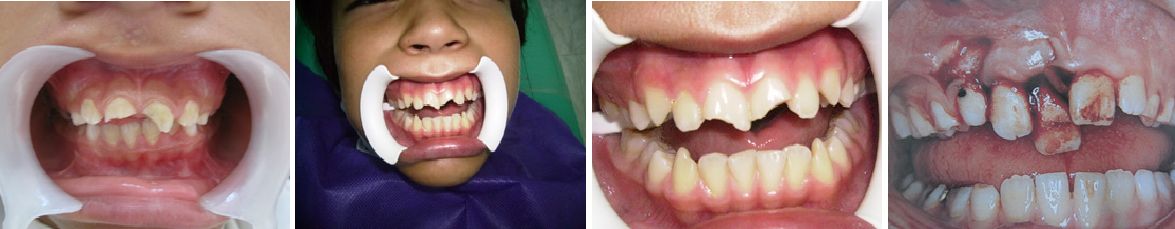

PACIENTE CON TRATAMIENTO FINALIZADO

Optima rehabilitación lograda en 6 meses de tratamiento, donde la educación de la familia fue factor fundamental de éxito